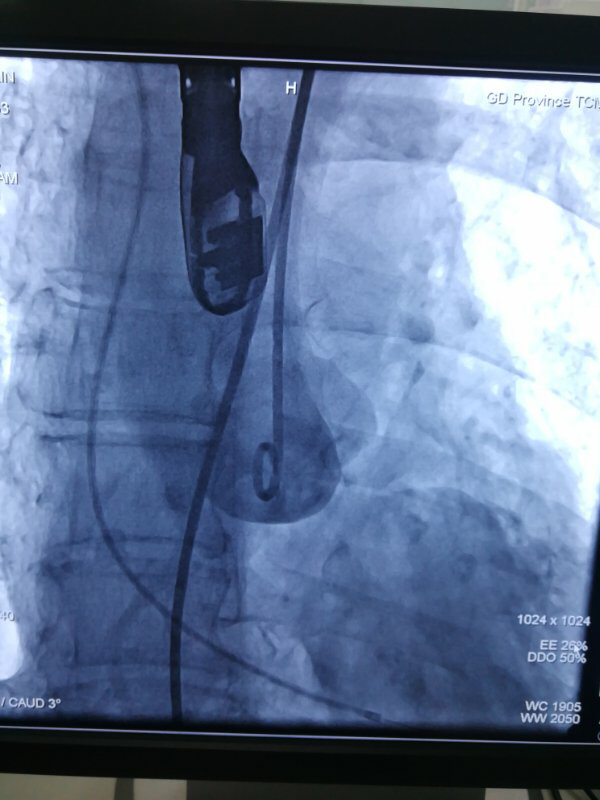

术中,在TAVI心脏手术团队的协作下,首先在患者心尖部位开一小孔,然后操控一根细长的输送鞘,将人工生物心脏瓣膜送入患者心腔。在造影屏幕监视下,新瓣膜被准确定位和放置于病变主动脉瓣位置。原来的心脏泵血“阀门”因关不紧“漏水”,新瓣膜“安装”完毕后,就像一扇运行良好的新“阀门”,一张一合地开始工作了。

图片说明:造影评估主动脉根部结构。

图片说明:人工瓣膜释放。